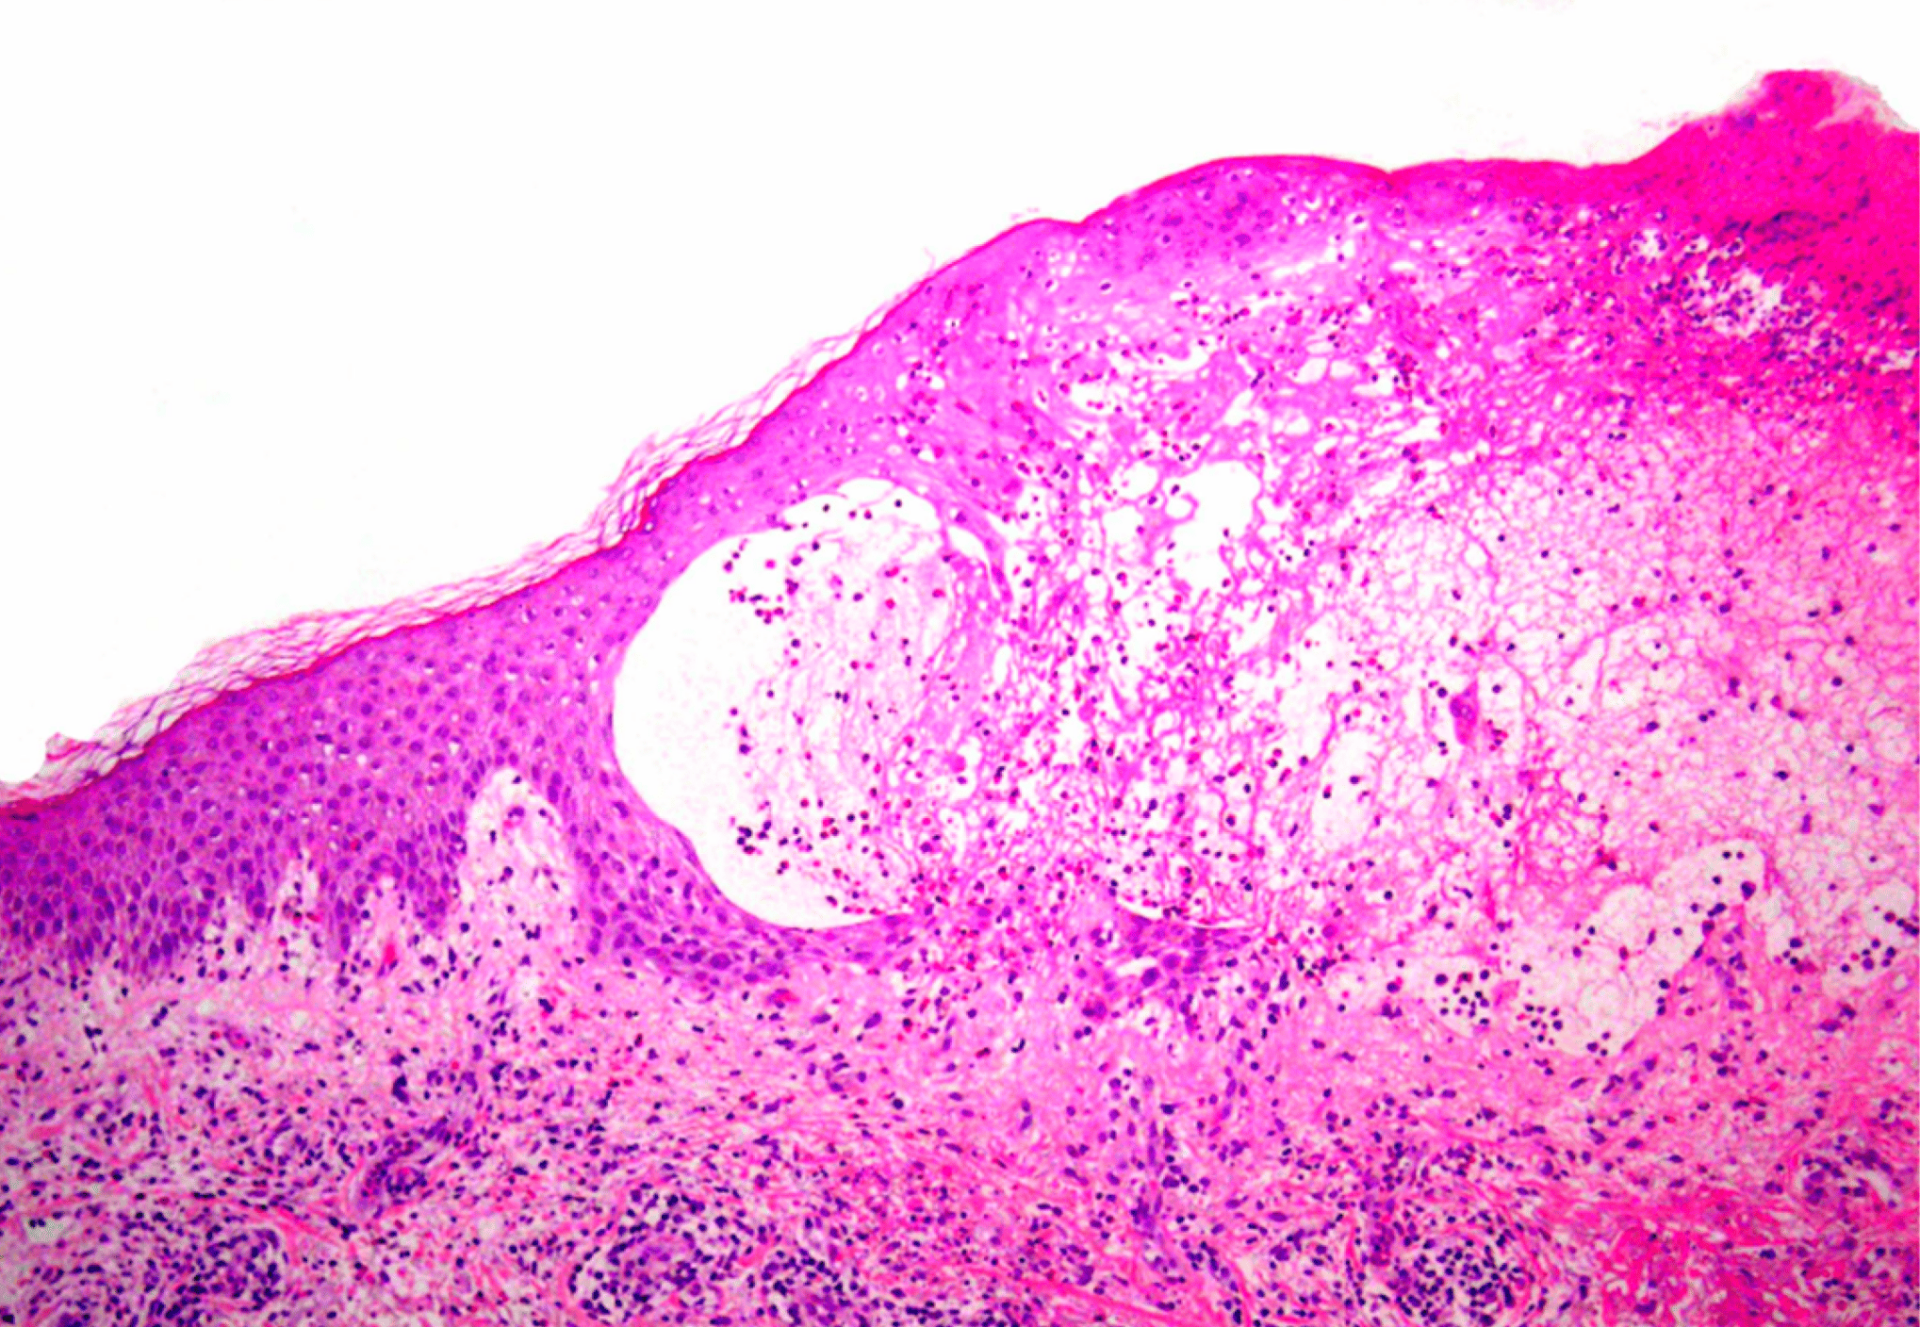

Direkte und indirekte Immunfluoreszenz sind beim bullösen Pemphigoid nach wie vor der Goldstandard für den Nachweis spezifischer Antikörper und Autoantikörper. Als Erstlinientherapie werden hochwirksame topische Steroide oder systemische Kortikosteroide empfohlen. Bei mangelndem Ansprechen oder Kontraindikationen kann auf immunmodulatorische und immunsuppressive Medikamente ausgewichen werden. Omalizumab und Dupilumab haben sich gemäss mehrerer Fallberichte als wirksame Therapieoptionen erwiesen und weitere Biologika werden aktuell erforscht.